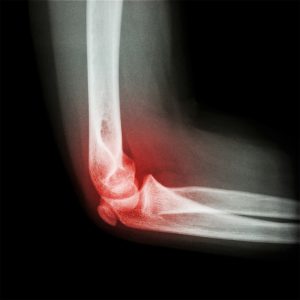

Elbow and forearm scan

Ultrasound scan of the elbow can look at the joint, the tendons, muscles, and ligaments. It also looks for bursa and soft-tissue swelling.

Commonly seen due to pain in the elbow on either side of the elbow (known as tennis elbow or golfer’s elbow) is due to inflammation of the tendons.

Elbow scan £135